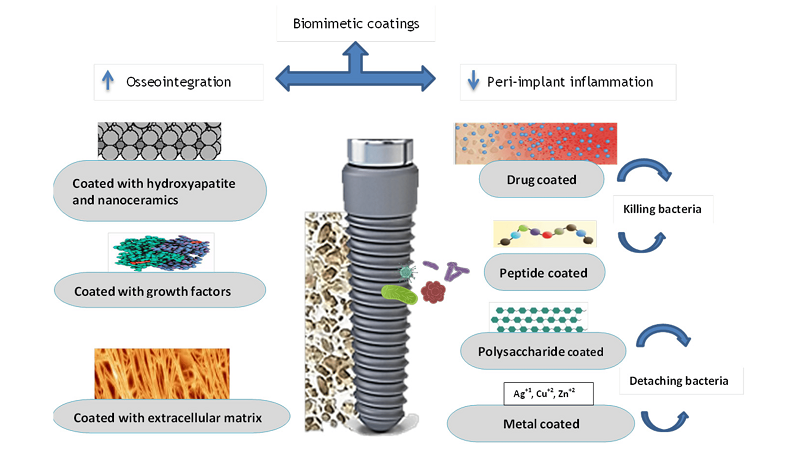

- ایمپلنت دندان اصفهان

درد دندانهای مجاور پس از کاشت ایمپلنت یکی از مشکلاتی است که برخی بیماران تجربه میکنند. این در...